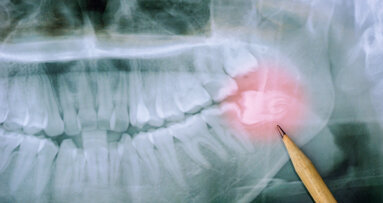

DÜSSELDORF - Die S2k-Leitlinie zur „Operativen Entfernung von Weisheitszähnen“ liegt jetzt in einer aktualisierten Fassung vor.